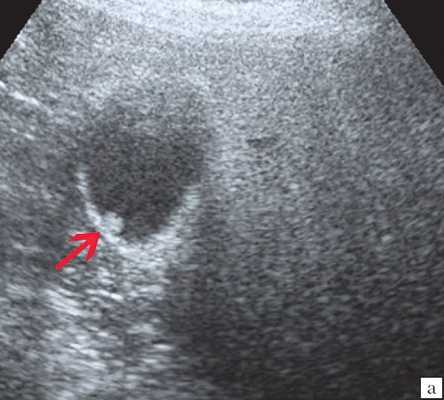

Ультрасонография является эффективным средством выявления полиповидной формы холестероза 6. Традиционной считается следующая сонографическая характеристика холестериновых полипов: неподвижные гиперэхогенные структуры, которые не дают акустической тени и прикрепляются к стенке желчного пузыря. Контуры таких образований, как правило, ровные, а размеры таких образований различны, чаще не превышают 10 мм (рис. 2).

a) Одиночный полип в желчном пузыре (гиперэхогенное пристеночное неподвижное образование, с ровными контурами, без акустической тени).

г) Одиночный полип в желчном пузыре.